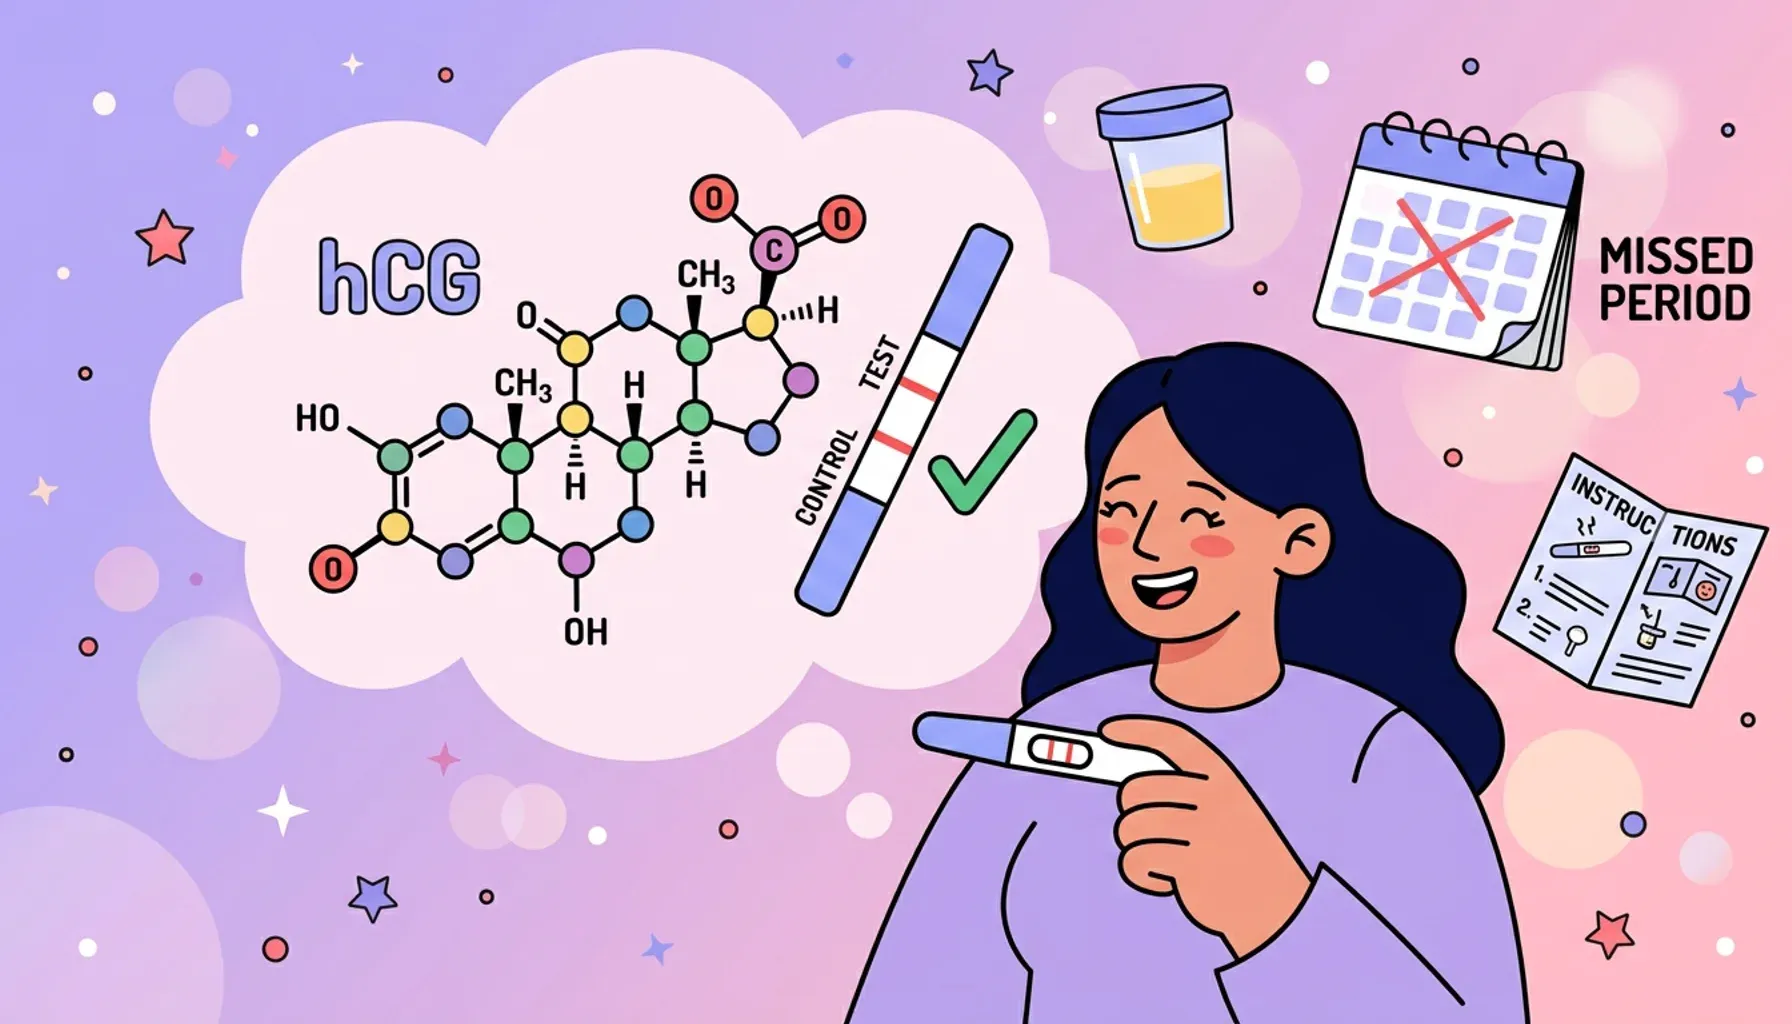

How pregnancy tests work

Learn how pregnancy tests detect hCG hormone and work to confirm your healthy pregnancy.

Let’s talk about hCG

Learn about hCG pregnancy hormone levels, when they can be detected, normal ranges, and what high or low levels indicate.